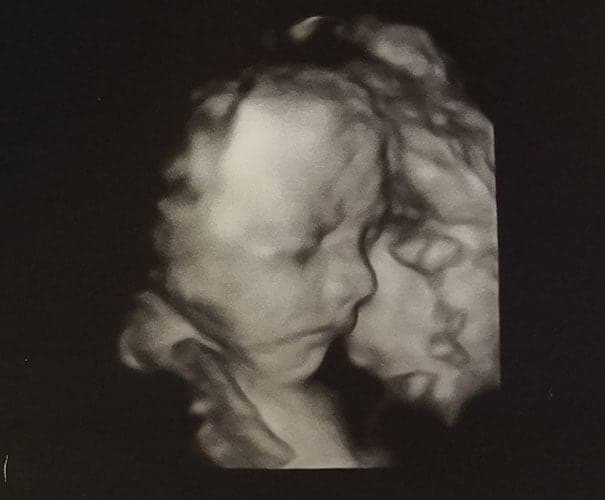

Ultraschallbilder aus dem 3. Trimester (29. bis 40. SSW)

Im dritten Trimester der Schwangerschaft ist das Baby so groß, dass es nicht mehr komplett auf ein Ultraschallbild passt. Nun kann man wunderbare 3D-Ultraschalle des Gesichts machen. In diesem Semester nehmen die Babys nochmal rasant zu und wer Glück hat, kann auf seinem Ultraschall schon erste Gesichtszüge erkennen.

Wer sich jedoch erhofft Gesichtszüge zu erkennen, der wird oft enttäuscht. Zwar kann man beim 3D-Ultraschall schon eine Menge sehen, aber das umgebende Fruchtwasser sorgt in den allermeisten Fällen für starke Störungen.